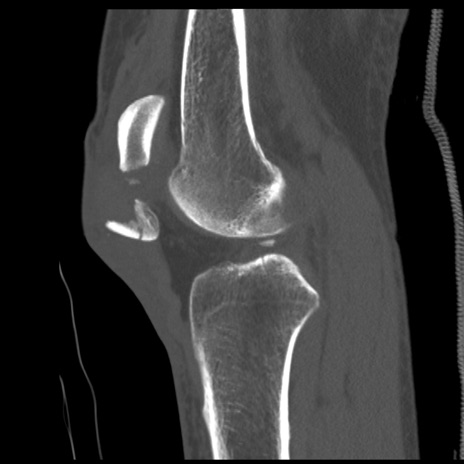

症例28 右膝関節CT(矢状断像)

右膝関節CT